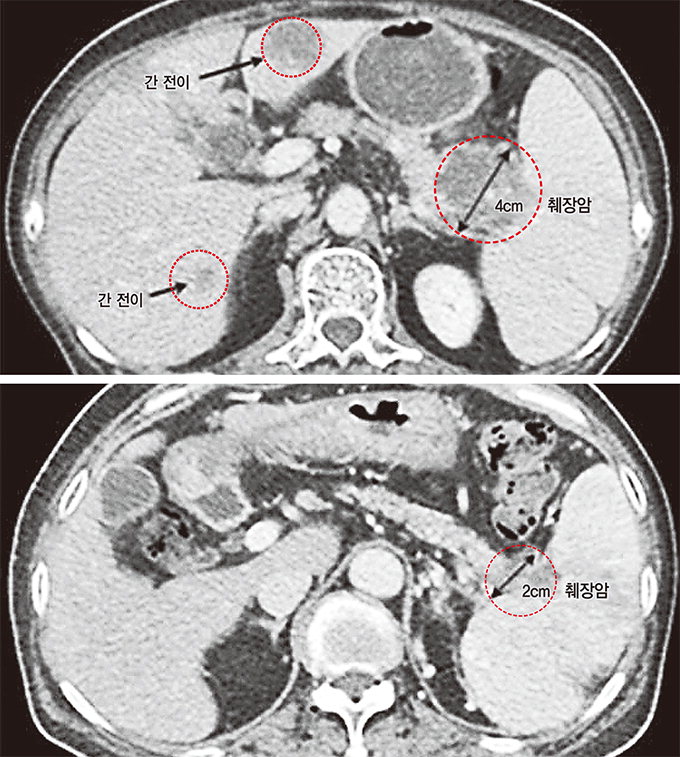

췌장암 초기증상

췌장암의 경우 중기 및 진행기의 환자가 많다. 즉, 요통을 앓고 있다면 불행히도 췌장암은 상당히 진행된 상태입니다. 암세포가 췌장 주변의 신경으로 퍼지면 상복부나 등에 심한 통증을 유발할 수 있습니다. 또한 요통이 아니라 복통이 있다면 암세포가 췌장 주변으로 퍼졌다는 뜻입니다. 통증이 없는 치료에 비해 치료 후 진행이 좋지 않기 때문에 정기적인 검진이 중요합니다.